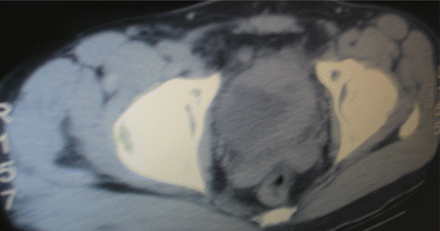

A 43-year-old African immigrant from Mali to the United States, whohad intermittent hematuria for 36 years. What does this image demonstrate? What are the next steps for diagnosis and treatment?